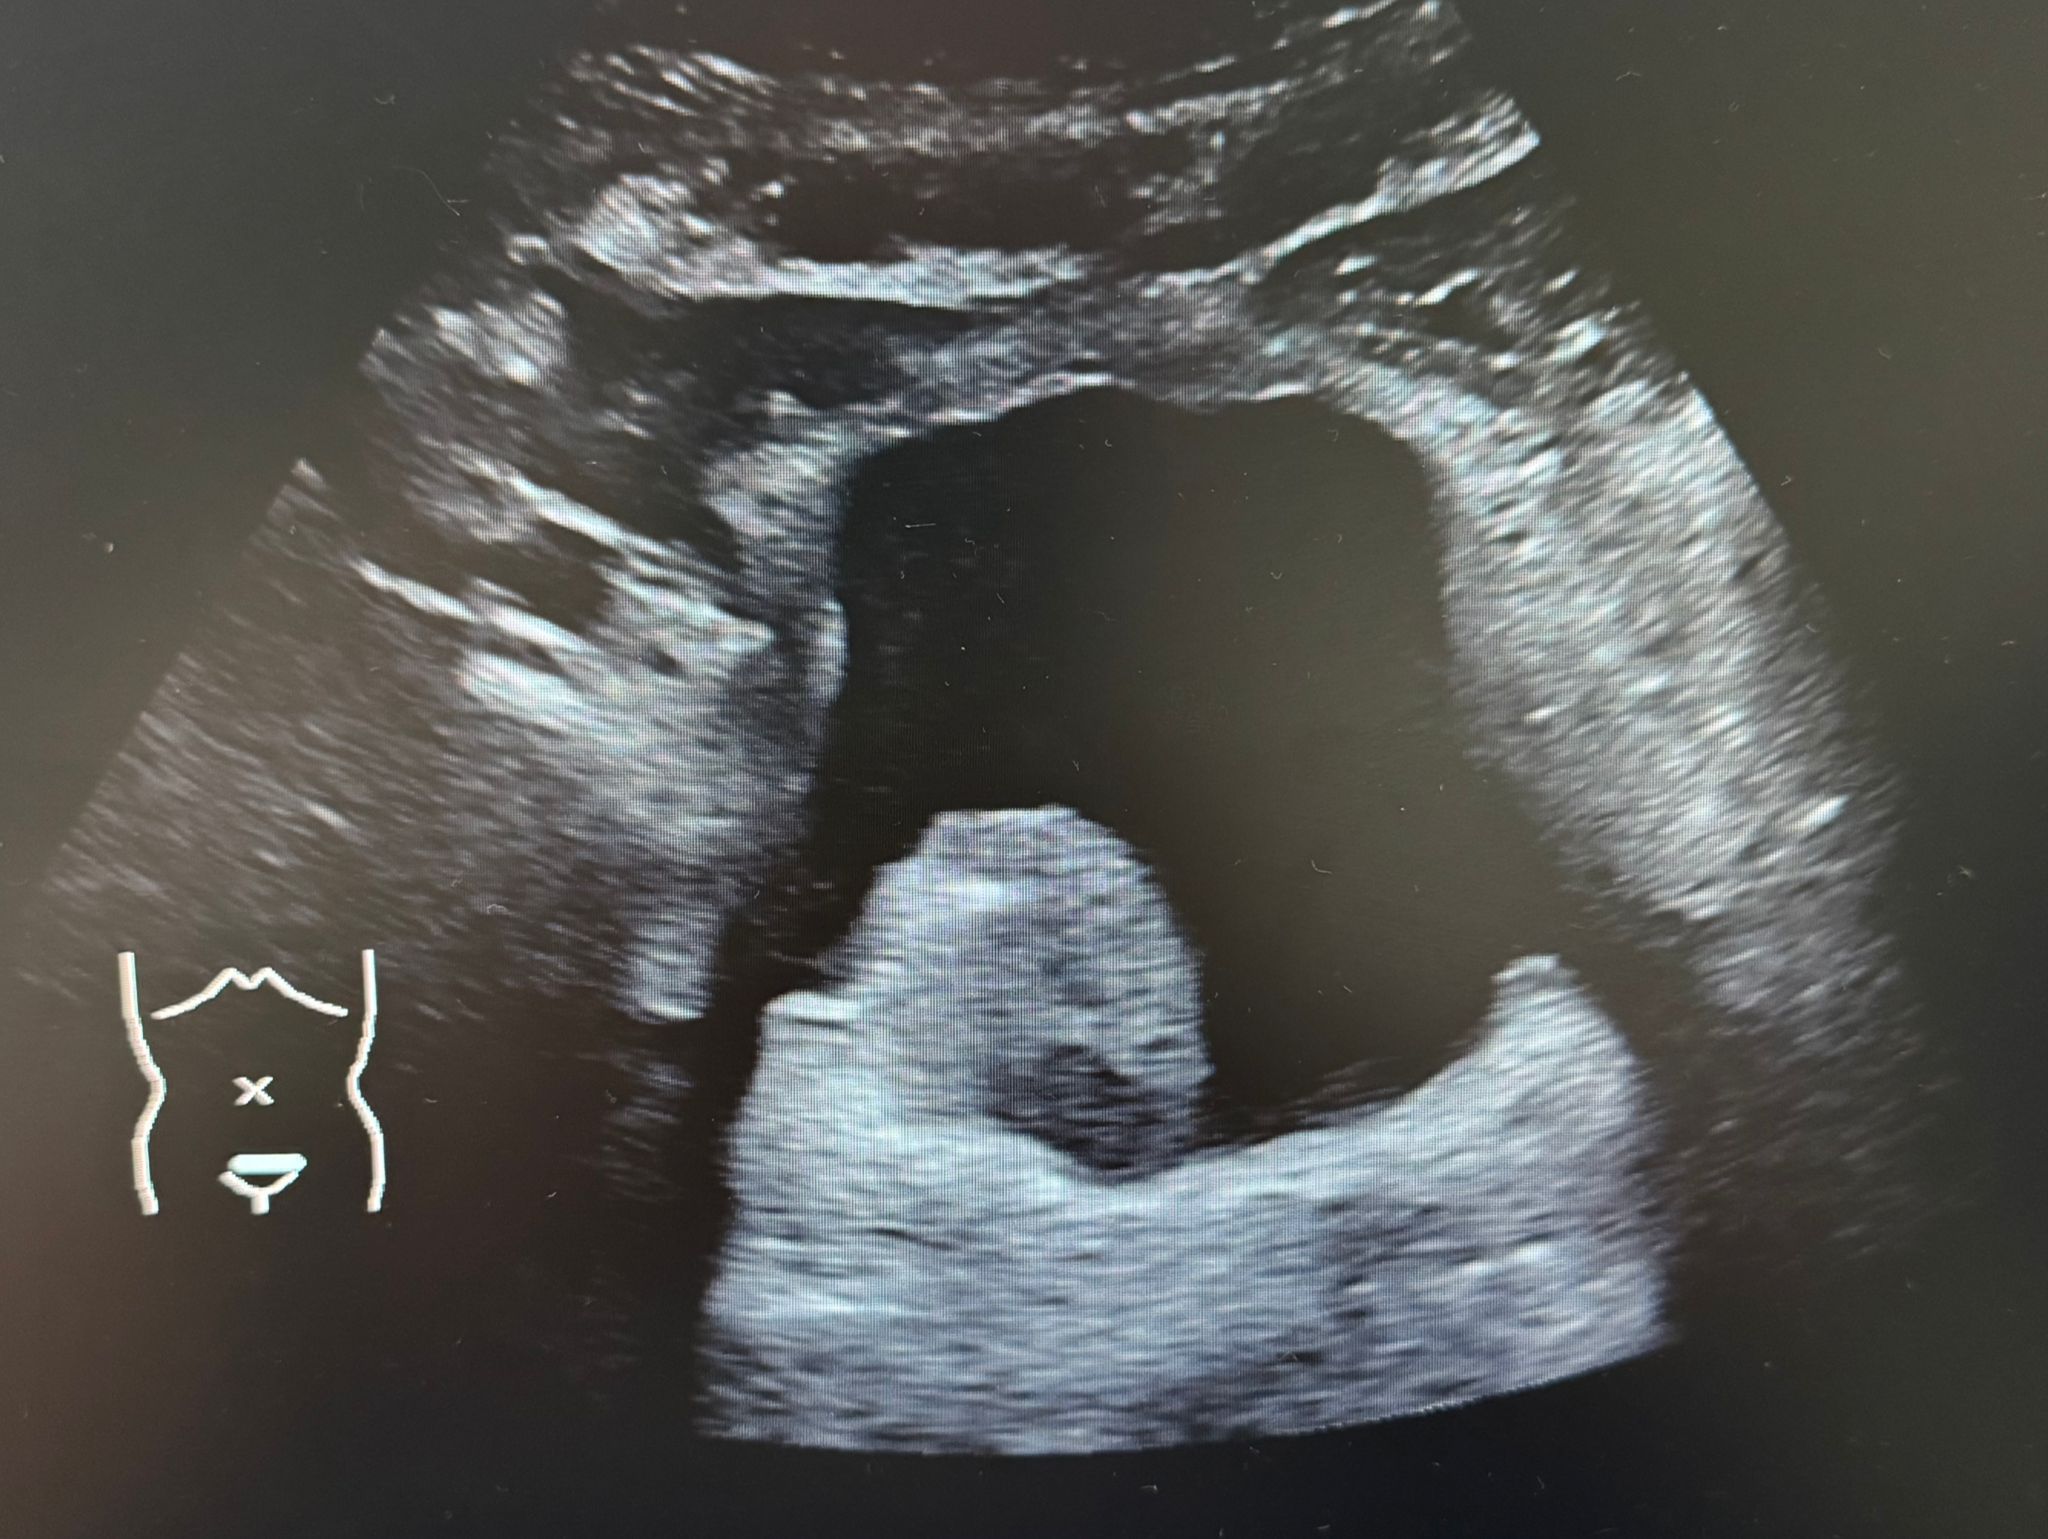

Se realiza ecografía abdominal a pie de cama donde destaca un nódulo heterogéneo y polilobulado a nivel endoluminal vesical, de 4x3 cm, altamente vascularizado. Hígado de tamaño y ecogenicidad normal, no se objetivan LOES. Resto de la exploración sin hallazgos.